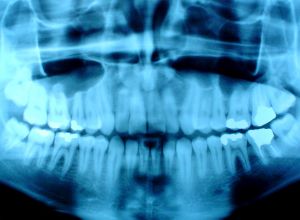

Digital X-Ray

Digital x-rays are quickly becoming the standard in dental imaging.

Digital x-rays allow the doctor to get a much better view of your teeth and potential dental conditions. The digital imaging software allows the doctor to see a number of different views of the tooth to gain a better understanding of the proper course of management. Digital x-rays provide a great benefit to the patient. Not only are they an excellent diagnostic tool, but they decrease radiation to the patient by over 80%.